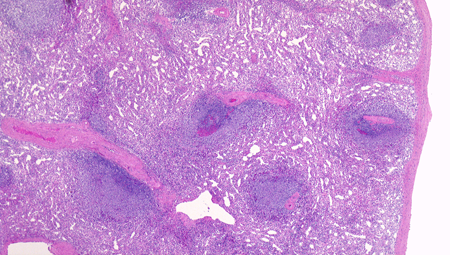

脾臓の組織所見

赤脾髄の構造 Structure of the red pulp

splenicsinus04.png

spleenRp03b.png

脾臓を灌流固定で赤血球を除いています。

左図:赤脾髄の拡大像 1. 脾洞 2.脾索が見えます。

右図:赤血球の残った部分です。脾洞に入り込む赤血球が見えます。

白脾髄の構造 Structure of the white pulp